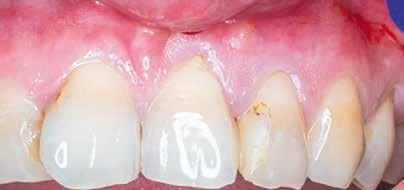

A gyökértömés elkészítése során meleg vertikális kompakciós technikát alkalmaztunk, sealerként pedig CeraSeal-t (Meta Biomed; 3. ábra) használtunk. A reszorbciós üreget Biodentine-nel (Septodont; 4. a–b ábra) töltöttük fel. A reszorbcióval érintett területtől koronális irányba elhelyezkedő csatornaszakaszt pedig tisztán meleg guttaperchával kezeltük. Ezt követően a lebenyszéleket visszafektettük, és varratok behelyezésével eredeti pozíciójuknak megfelelően rögzítettük. A koronai részt kompozit tömőanyag segítségével állítottuk helyre. Kontrollvizsgálatra 5, illetve 30 hónappal később került sor (5. ábra). A csontos telődés jelei már 5 hónap után észlelhetők voltak (6. a–c ábra). A 30 hónappal később végzett kontroll során sem találtunk csontban lévő lézióra, törésre vagy egyéb pathológiás elváltozásra utaló jeleket (7. a–b ábra)

Második esetbemutatás

A 28 éves pácienst gyulladásos IRR kezelése céljából irányították a rendelőnkbe. A jobb felső nagymetszőfogáról készített periapikális röntgenen egyértelműen látható volt a lézió. A várható prognózis megállapítása, valamint kezeléstervezés céljából az érintett területről CBCT-felvétel készült (8. a–e ábra). A háromdimenziós képen látható volt a gyökér labiális falán lévő perforációs nyílás, valamint az ezt körülvevő bukkális kortikális destrukciója. A terület sebészi feltárását a bal felső nagymetszőfogtól a jobb felső szemfogig intrasulcularisan vezetett metszésből végeztük el. A lebeny elemelését követően egy exkavátor segítségével eltávolítottuk a reszorbciós üreget kitöltő granulációs szövetet (9–11. ábra), majd hagyományos

MTA-val (Mineral Trioxide Aggregate; Harvard Dental) töltöttük fel. A léziótól koronális irányban elhelyezkedő gyökércsatorna-szakaszt meleg guttaperchával zártuk, majd az MTA-val kitöltött üregre egy kis darab kollagénszivacsot helyeztünk és a lebenyt varratok segítségével eredeti pozíciójában rögzítettük (12. a–b; 13. a–b. ábra). A fog koronai részét Gradia kompozit tömőanyaggal állítottuk helyre (GC; 14. a–b; 15. ábra). Kontrollvizsgálatra két (16. a–b ábra) és négy évvel (17. a–b ábra) később került sor. A kontrollfelvételeken a bukkális kortikális jelenléte volt észlelhető. A fog körüli parodoncium egészséges volt, valamint a páciens sem számolt be tünetekről.

9. a–b ábra: A műtét előtt (a) és a lebeny felemelését követően látható állapot (b). – 10. a–d ábra: A granulációs szövet eltávolítása.

13. a–c ábra: A reszorbtív üreg bioanyaggal való feltöltése és a kollagénszivacs elhelyezése. – 14. a–b ábra: Posztoperatív röntgen (a), a varratok behelyezését követően látható klinikai helyzet (b).

15. ábra: A 14 nappal később látható állapot.

11. a–b ábra: A gyökércsatorna átöblítése.

12. a–b ábra: A gyökértömés elkészítése.